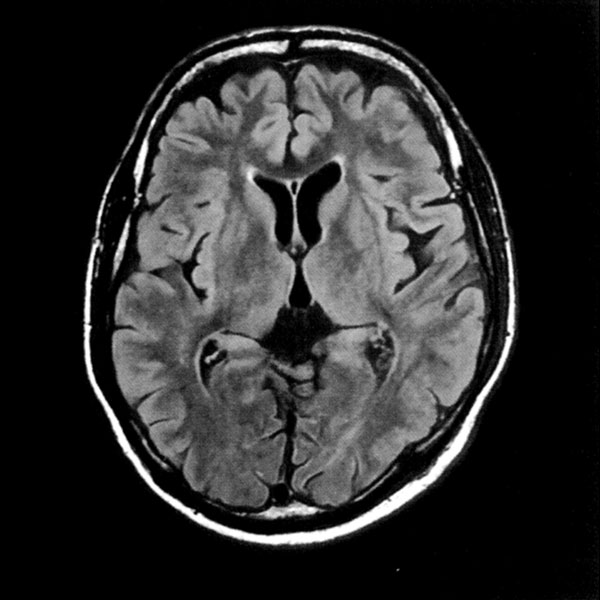

MRI検査

2025年9月16日スタート!!1.5T MRI SIGNA Creator(GE社製)

新しいMRI装置では従来の装置と比較し、高画質、かつ短時間での検査が可能となります。

- AI 機能を搭載:従来の装置と比べかなりの高画質が期待できます

- 従来の装置では難しかった微細な変化の描出にも期待がもてます